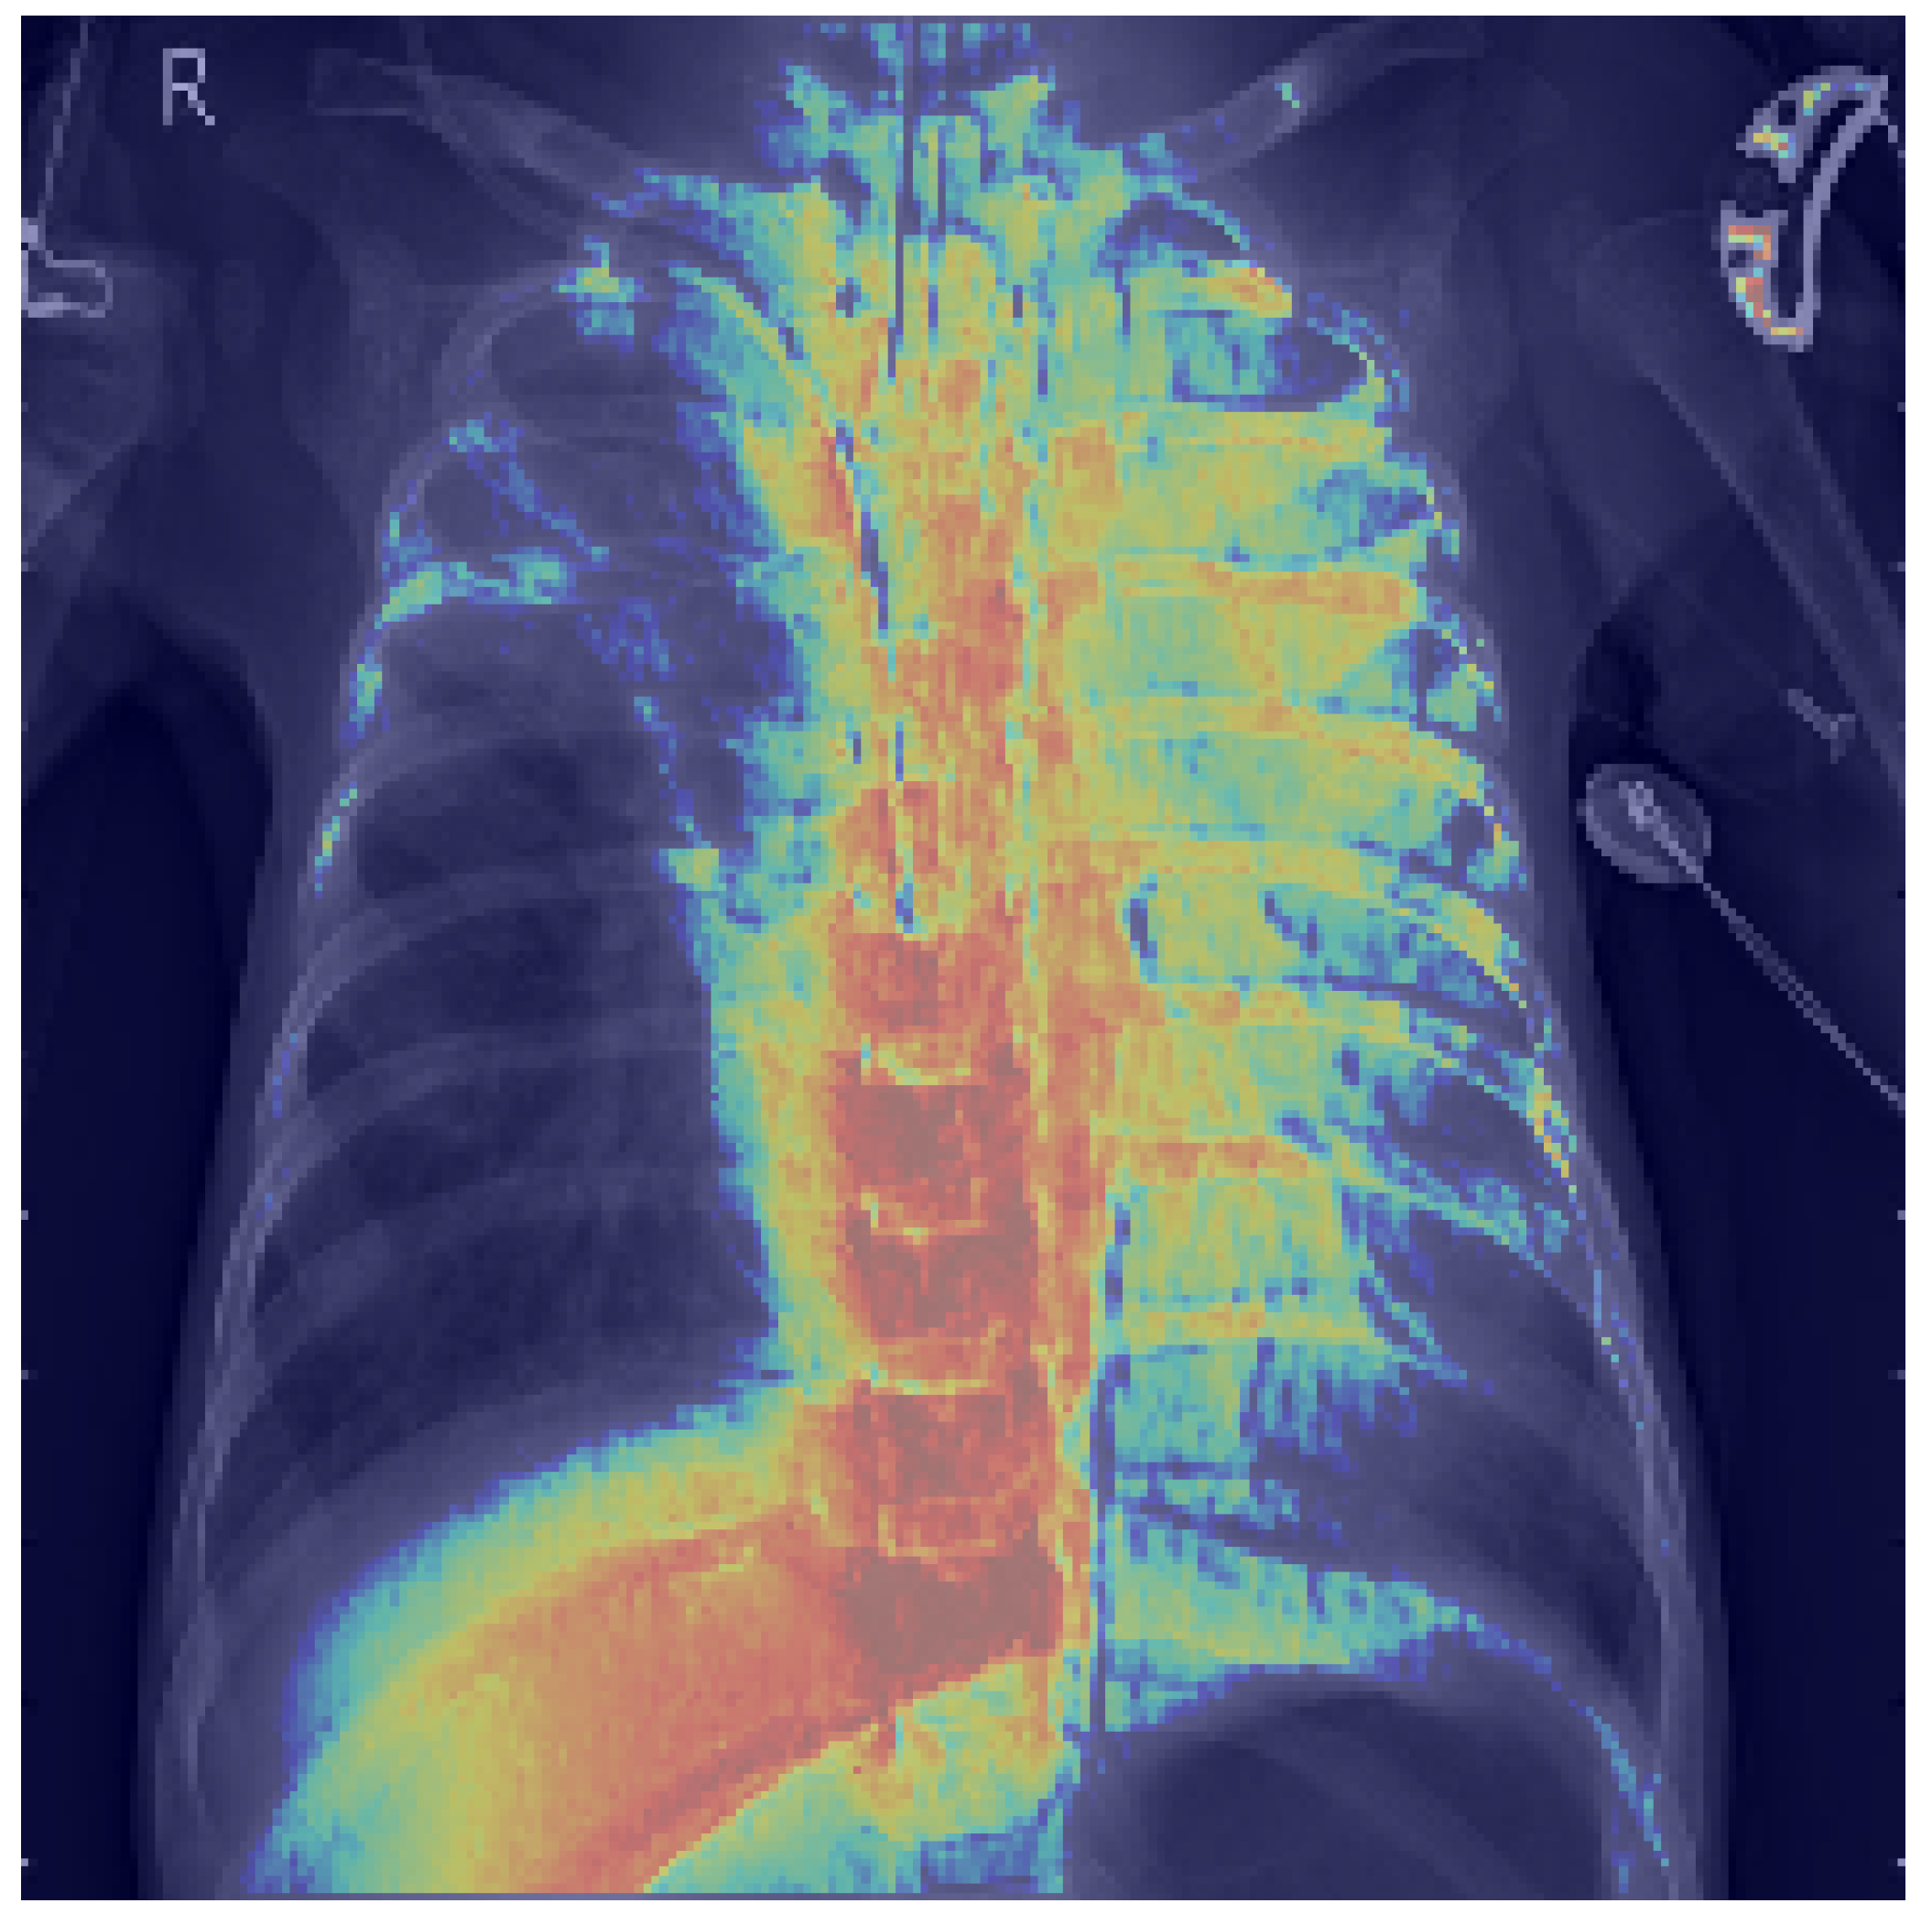

3.8. Explainability Analysis

4. Results